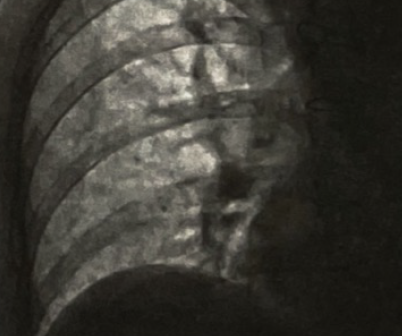

患者行胸部CT(图3)显示右肺下叶节段性膨胀不全,未见气胸表现,同时可见双侧胸腔少量积液,心影增大不明显,暂排除肺部感染、气胸、心力衰竭疾病,X线胸片(图4)提示右侧膈肌上抬,透视检查可见右侧膈肌抬高,运动幅度明显减弱(图5)。常见引起膈肌抬高的常见原因有:①肝脏占位、脓肿;②肺不张引起肺容积缩小;③膈肌麻痹。结合此患者房颤消融史,考虑可能为房颤射频消融术引起了膈神经损伤,然后出现了膈肌麻痹。

(4).png)